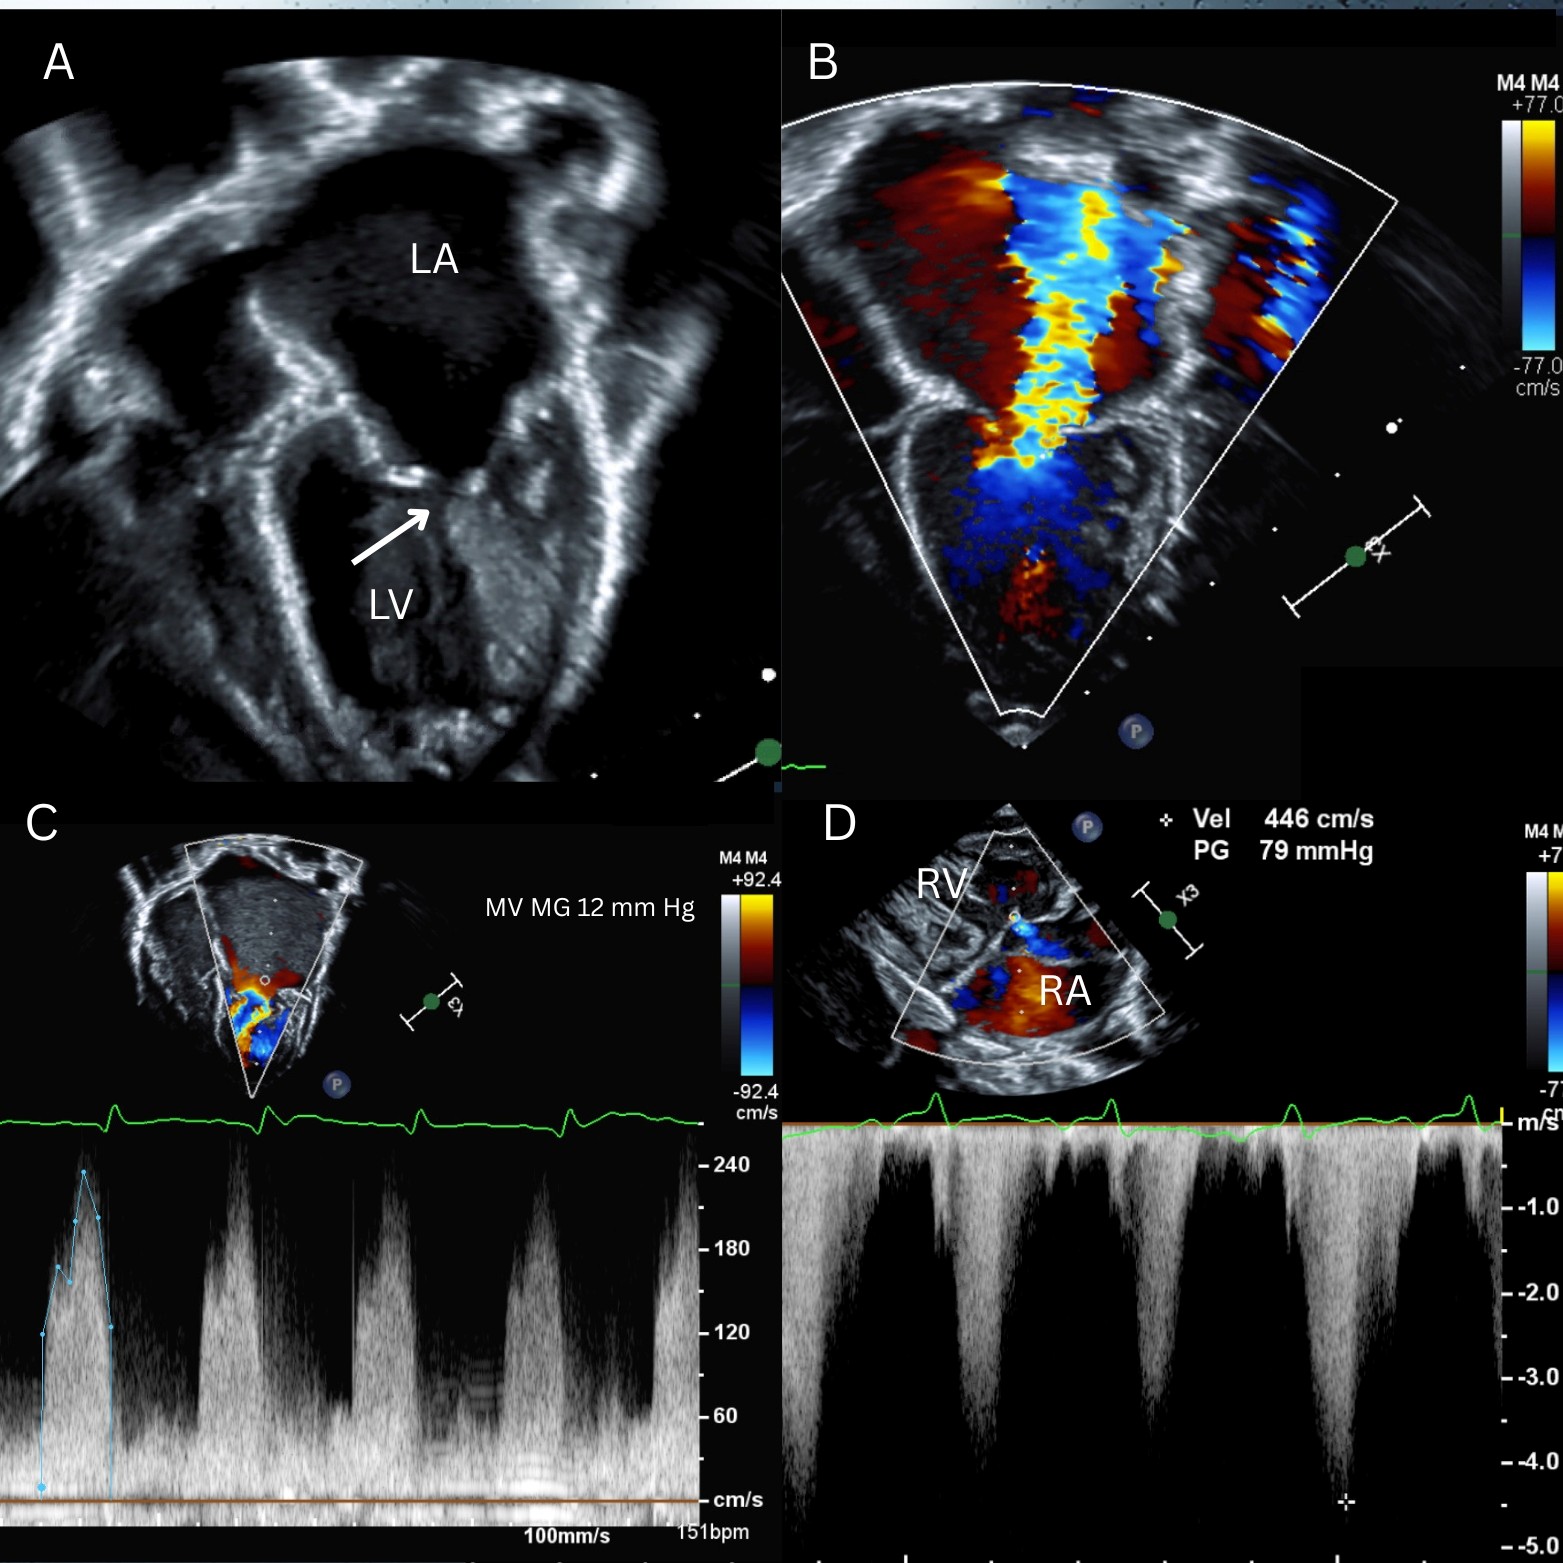

Congenital malformations of the MV can present in the neonatal period with symptoms of pulmonary venous congestion such as increased work of breathing, tachypnea, and failure to thrive secondary to left atrial (LA) hypertension. This patient presented with decompensated heart failure (HF) secondary to significant mitral stenosis (MS) and mitral regurgitation (MR) attributable to an arcade MV. Image 1, panel A (arrow) shows a mitral arcade characterized by elongated papillary muscles connected to each other and to the free edge of the anterior mitral leaflet by a bridge of fibrous tissue as a result of muscularization of the subvalvular apparatus.1 This malformation can lead to MS, MR, or both. This neonate had a severely dilated LA and mildly dilated left ventricle (LV) (Image 1, panel A) with severe MR (Image 1, panel B) and mean gradient 12 mm Hg at resting HR 151 bpm across the MV (Image 1, panel C). In the setting of severe MR, assessment of MS can be challenging because the gradient across the MV can be exaggerated due to increased flow (pulmonary venous flow plus regurgitant volume).